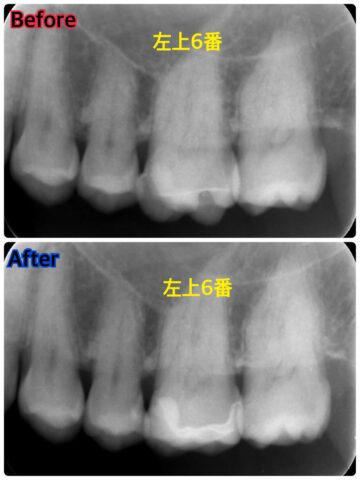

治療前後の比較がこちらです。

この歯は部分的なセラミックスの詰め物で治療を行います。